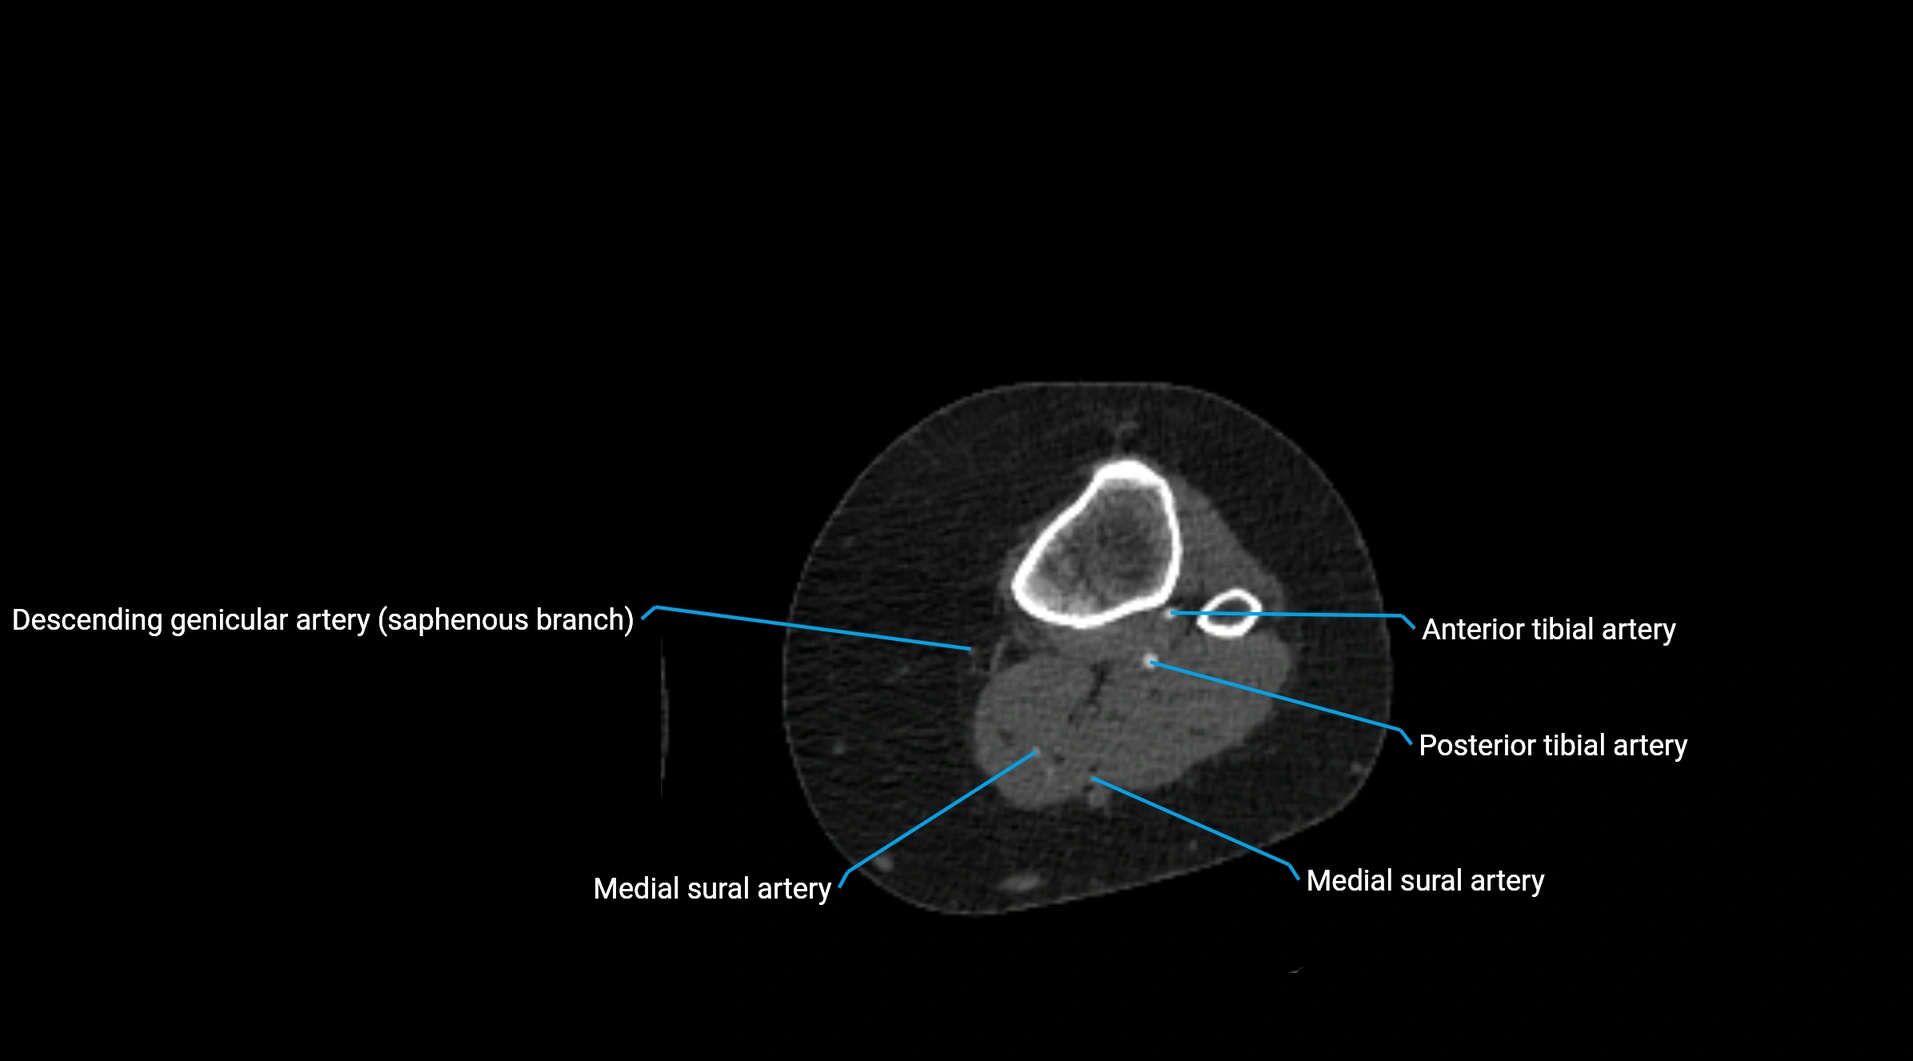

CT Appearance

Non-contrast CT:

• Appears as a tubular soft tissue structure anterior to vertebral bodies

• Calcified atherosclerotic plaques appear as hyperdense foci along the wall

• Useful for screening abdominal aortic aneurysm (AAA) size and mural calcification

Contrast-enhanced CT (CTA):

• Gold standard for abdominal aortic imaging

• Provides excellent detail of lumen, wall, aneurysm, thrombus, and branch vessels

• Multiplanar and 3D reconstructions help in aneurysm measurement, stent graft planning, and dissection evaluation

• Detects acute rupture, traumatic injury, or occlusion with high sensitivity